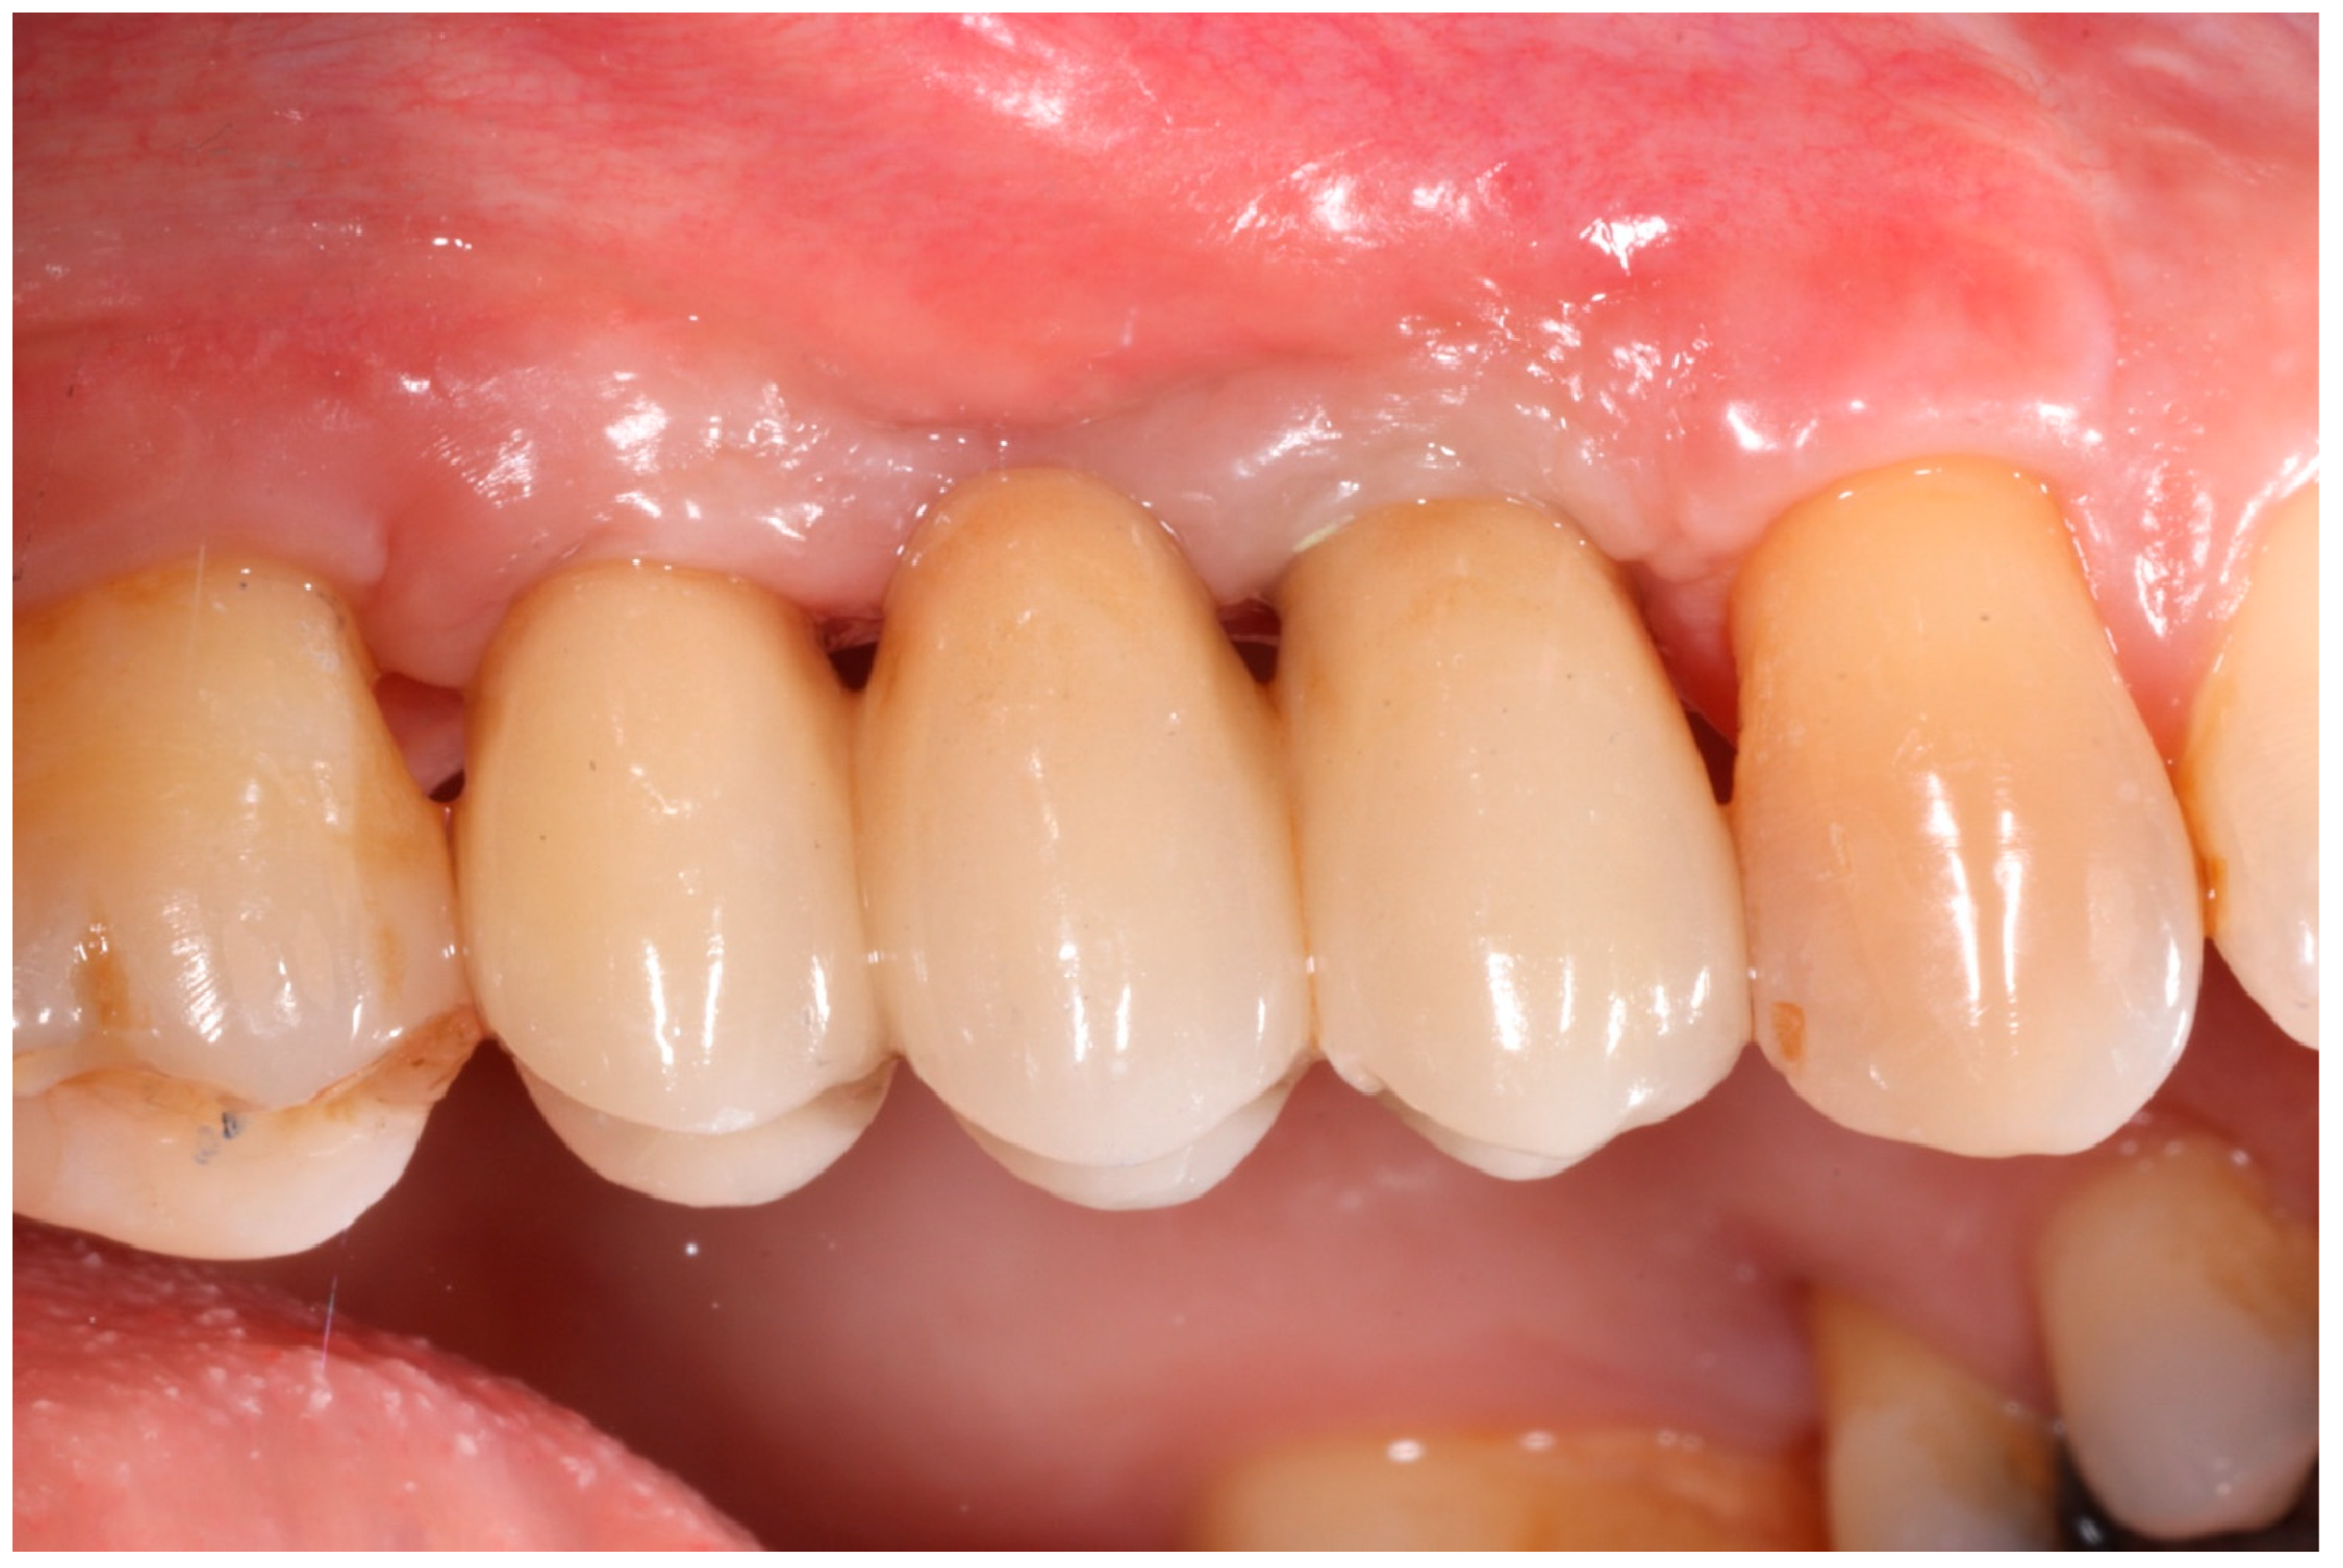

Healing abutments were screwed to the implants and the flaps were sutured. Additional peri-implant plastic surgery procedures (connective tissue grafts or free gingival grafts) were performed when needed in order to have at least 2 mm of attached keratinized mucosa. The prosthetic phases began upon healing of the soft tissues, and definitive screw-retained prostheses were finally delivered (Figure 11, Figure 12 and Figure 13).

Figure 11. Delivery of definitive prosthesis.